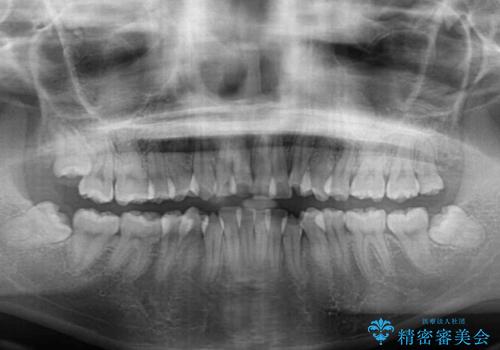

- 上下前歯の叢生と八重歯を気にして来院された患者様です。

前歯部叢生のスペースを獲得するため、上下顎左右小臼歯各1歯を抜歯することとしました。